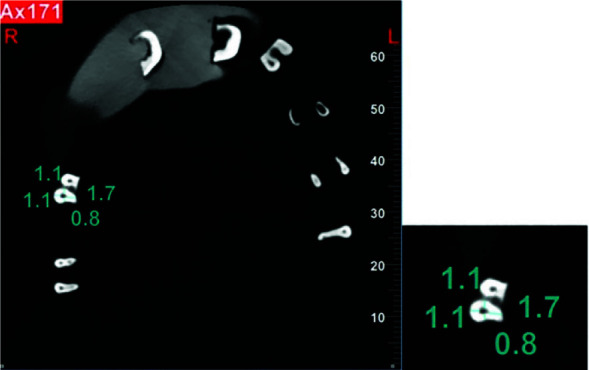

Materials and method: In this in vitro experimental study, eighty primary molar roots were randomly assigned to four groups. Cone-beam computed tomography (CBCT) scans were provided for the samples, and hand files (group 1), Mtwo (group 2), Reciproc (group 3), and Gentlefile (group 4) were used to instrument the root canals. Once more, CBCT scans were acquired, and at 1, 2, and 3mm from the apex as well as 1 mm from the orifice, the canal transportation and centering ability were evaluated in buccolingual and mesiodistal directions. Zeolite (ZOE) cement was used to obturate every root canal. To evaluate the obturation density, number of voids, and underfilling in each group, new CBCT scans were obtained. For every tooth, the maximum, minimum, and average Hounsfield units (HU) were noted. One-way ANOVA, the Kruskal-Wallis test, and Tukey's HSD test were used to analyze the data.

Results: Mtwo exhibited considerably superior centering ability than Gentlefile at 2mm from the apex in the mesiodistal direction (p Value< 0.05). Gentlefile had significantly higher buccolingual canal transportation than Reciproc at 3 mm from the apex (P0.05). Minimum HU, underfilling, and void numbers did not differ amongst the four groups (p= 0.791, p= 0.1, and p= 0.548). Reciproc had substantially higher maximum and average HU, followed by Mtwo, Gentlefile, and hand files (p< 0.05).